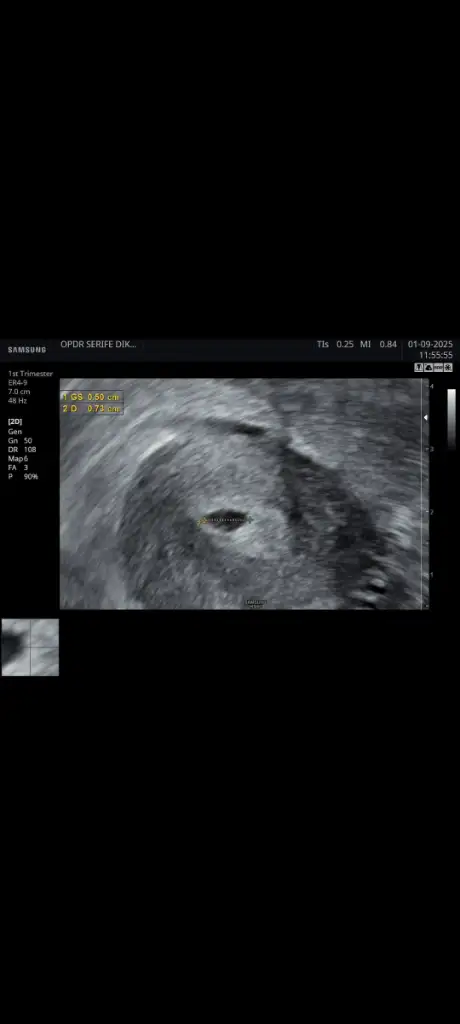

Hala kalp atışı yok ve kaç haftalık gebeyim onu bile bilmiyorum kalp atışı duyulmaması normalmi ultrason görüntüsüde ekliycem bilgisi olan varsa bana ne olduğunu anlatabilirmi

6 eylül de gittiğimde bana gelişimi yavaş ilaçları kes kendiliğinden vücut atsın dedi ama ben hala gelişim var diye biraz daha beklemek istedim yarın gene randevum var. Bana son adet tarihimden hesapladığını söyledi ama bu hesap yanlış diye biliyorum tüp bebek de embriyo transfer tarihinden hesaplanır diye biliyorum o yüzden biraz daha beklemek istedimDoktorun ne diyor